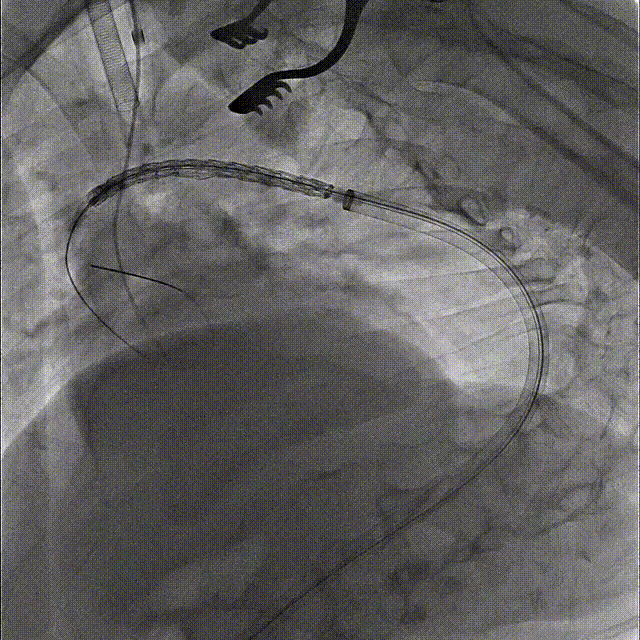

第一步、常规麻醉,消毒铺巾,分离显露左锁骨下动脉、左颈总动脉和左椎动脉备用。经右侧股动脉穿刺植入5F鞘,黄金标记猪尾导管升主动脉造影明确主动脉病变(图2)。

第二步、交换超硬导丝,置入Gore大鞘 DSF2065,顺利通过降主段以及主动脉缩窄处,近端到达无名动脉后缘。

第三步、经鞘内输送Gore TGU262610覆膜支架至无名动脉后缘释放。